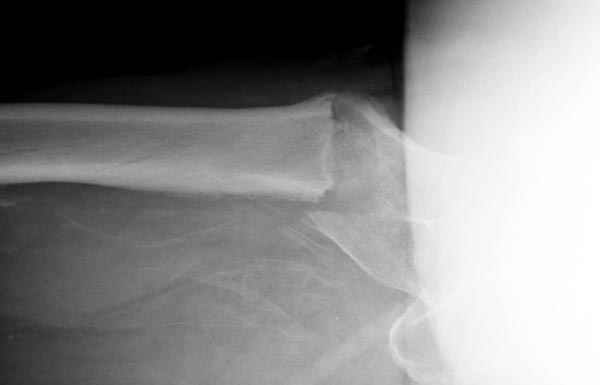

Изначально была выбрана не правильная точка введения стержня, в связи с чем в конце, я подчеркну, в конце операции произошло из-за напряжения между прокимальным концом канала бедра и стержнем разрушение в/3 бедра.

Проволока наложена потому, что при введении штифта не прошли эту зону римером и произошли сколы на концах отломков.

Зона раскола во время моей ревизии проходит по боковой поверхности как раз в зоне введения шеечного винта (картина как топор разрубил полено на две равных части, можа сделать КТ?)